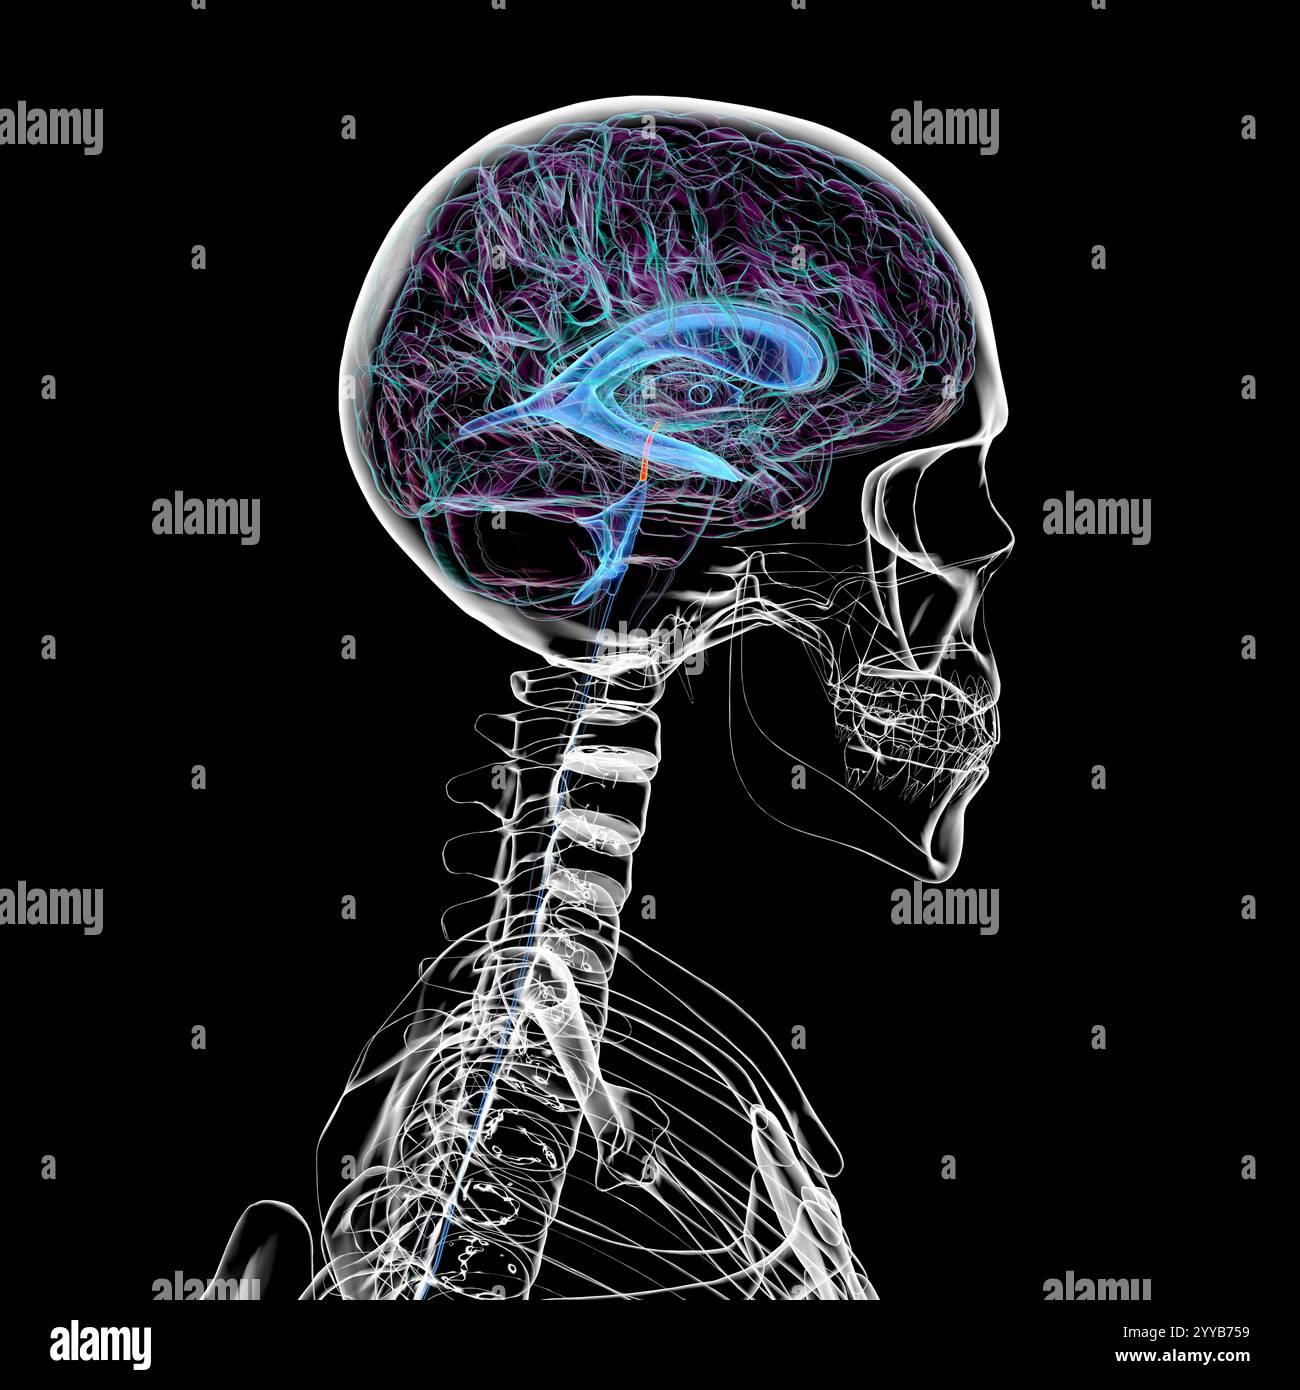

RF2T7NGWH–Ventrikel und zerebrales Aquädukt laterale Röntgenansicht 3D-Rendering-Illustration. Menschliches Gehirn und Ventrikelsystem Anatomie, Medizin, Gesundheitswesen, Scienc

RF2T7NGWK–Ventrikel und zerebraler Aquädukt lateral in Farben Röntgenbild-3D-Rendering-Illustration. Menschliches Gehirn und Ventrikelsystem Anatomie, medizinisch, gesund

RF2T7NGWR–Ventrikel und Hirn-Aquädukt-Röntgenprofil Nahansicht 3D-Rendering-Illustration mit Körperkonturen. Anatomie des menschlichen Gehirns und des Ventrikelsystems,

RF2T7NGWW–Ventrikel und zerebraler Aquädukt in Farben Röntgenprofil Nahansicht 3D-Rendering-Illustration. Anatomie des menschlichen Gehirns und des Ventrikelsystems, medizinisch,

RF2T030FH–Röntgenprofilansicht des Sylvius oder des zentralen Aquädukts des Gehirns 3D-Rendering-Illustration. Menschliche Körperanatomie, Medizin, Biologie, Wissenschaft, Neurowissenschaft,

RF2T6AR8J–3D-Rendering-Illustration für die Röntgenansicht des Gehirns oder des Sylvius aquädukt. Anatomie des menschlichen Gehirns und des Ventrikelsystems, Medizin, Gesundheitswesen, Biologie, Wissenschaft,

RF2T6AR96–Röntgenprofil des Gehirns oder sylvius aquädukt Nahansicht 3D-Rendering-Illustration mit Körperkonturen. Anatomie des menschlichen Gehirns und des Ventrikelsystems, med